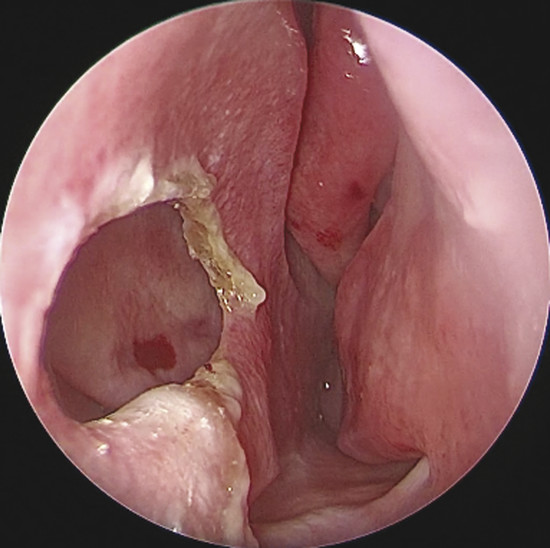

Upon physical examination of the nose, a full diagnosis cannot be made until all crusts have been removed and decongestion of the turbinates has taken place, making it possible to visualize the entire nasal septum. The nasal endoscopy allows appreciating the configuration of the NSP, the presence or absence of adherent crusts on the edges of the defect (Fig. 6‑1), any easily bleeding areas (Fig. 6‑2), and the state of the remaining mucosa, which may present some aspects regarding ischemic conditions (cocaine abuse) (Fig. 6‑3).

If the defect is not circular, but oval in shape (Fig. 6‑5), it is appropriate to obtain an exact measurement of the major diameters: anteroposterior and craniocaudal, vital in choosing the most appropriate surgical technique. The vertical height of a perforation has been predicted to play a more important role in determining the surgical success than the horizontal length because the main tension between the floor of the nose and the dorsum was critical. 2 The final aspect that must be considered for surgery is the location: anterior, posterior, near the floor, or in the cranial part of the septum. Septal spurs must be identified during endoscopic examination. These should be removed during flap harvesting to get one more large and flexible mucosal layer. (Fig. 6‑6). The septum should be palpated with a sticker or with a cotton tip to discern persistent cartilage between mucosal flaps and determine whether cartilage extends close to the edges of the NSP. 2 In perforations that have occurred after septoplasty, there is usually very little cartilage left, and this makes dissection of the flaps more difficult. In this phase it is also important to check the quality of other intranasal anatomical structures, which represented potential donor sites of grafts or flaps, such as the inferior turbinate, the middle turbinate or the floor of the nasal fossa.